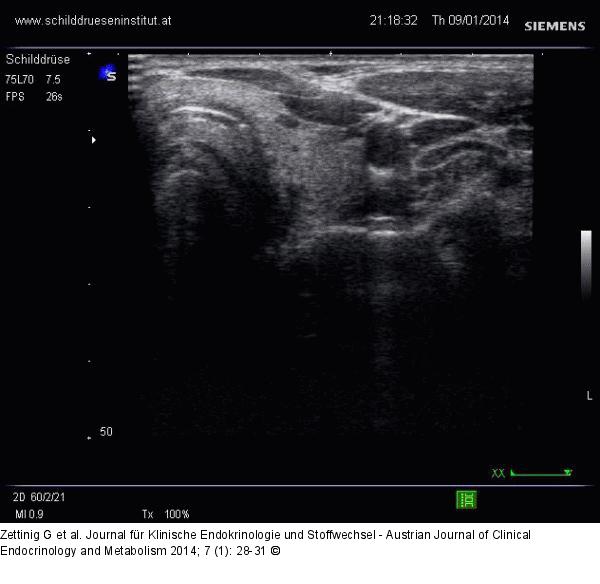

Abbildung 13: Video 5 - Linker Lappen

Linker Lappen im Querschnitt